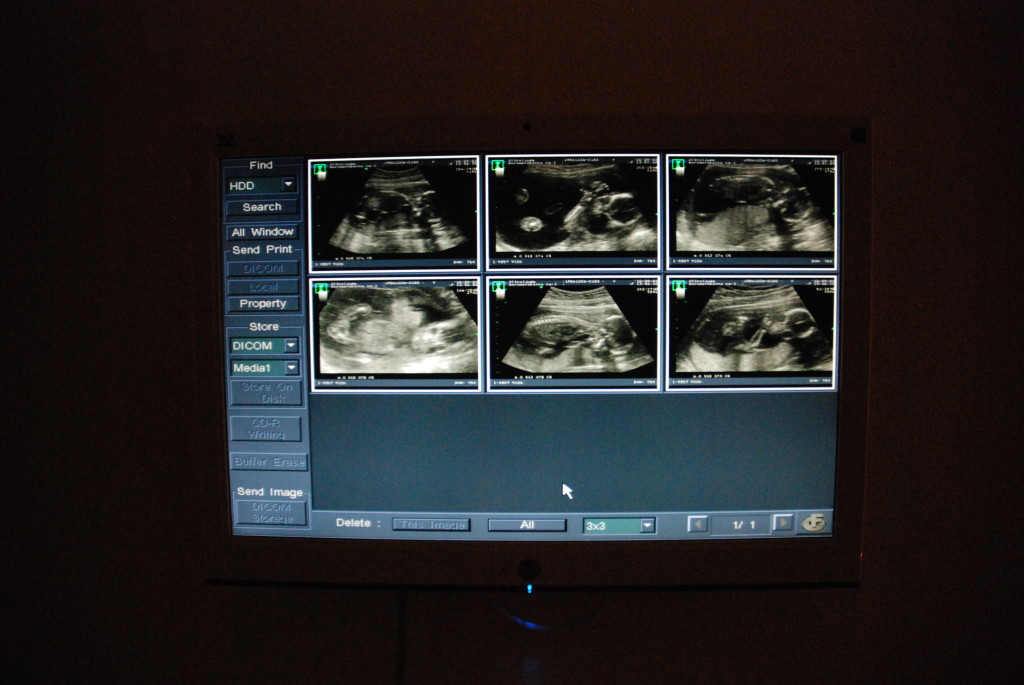

据说国内b超很频繁,这边奉行能少则少,认为这是在打扰小孩。10年怀老大的时候第一次b超是18周做的,然后36周的时候因为小孩没有转过来,就又超了一次。12年怀老二的时候瑞典改变了政策,是12周会做第一次b超用来排畸,18再做第二次。所以总体来说,整个孕期一般是做两次。而18周那次就可以确定性别了。如果是35周岁以上的高龄产妇12周还要做羊水穿刺。

b超的地方可以选择,本人两次去的都是liljholmen的那家,环境挺好的。b超是免费的,但是如果要b超照片的话是要钱的。